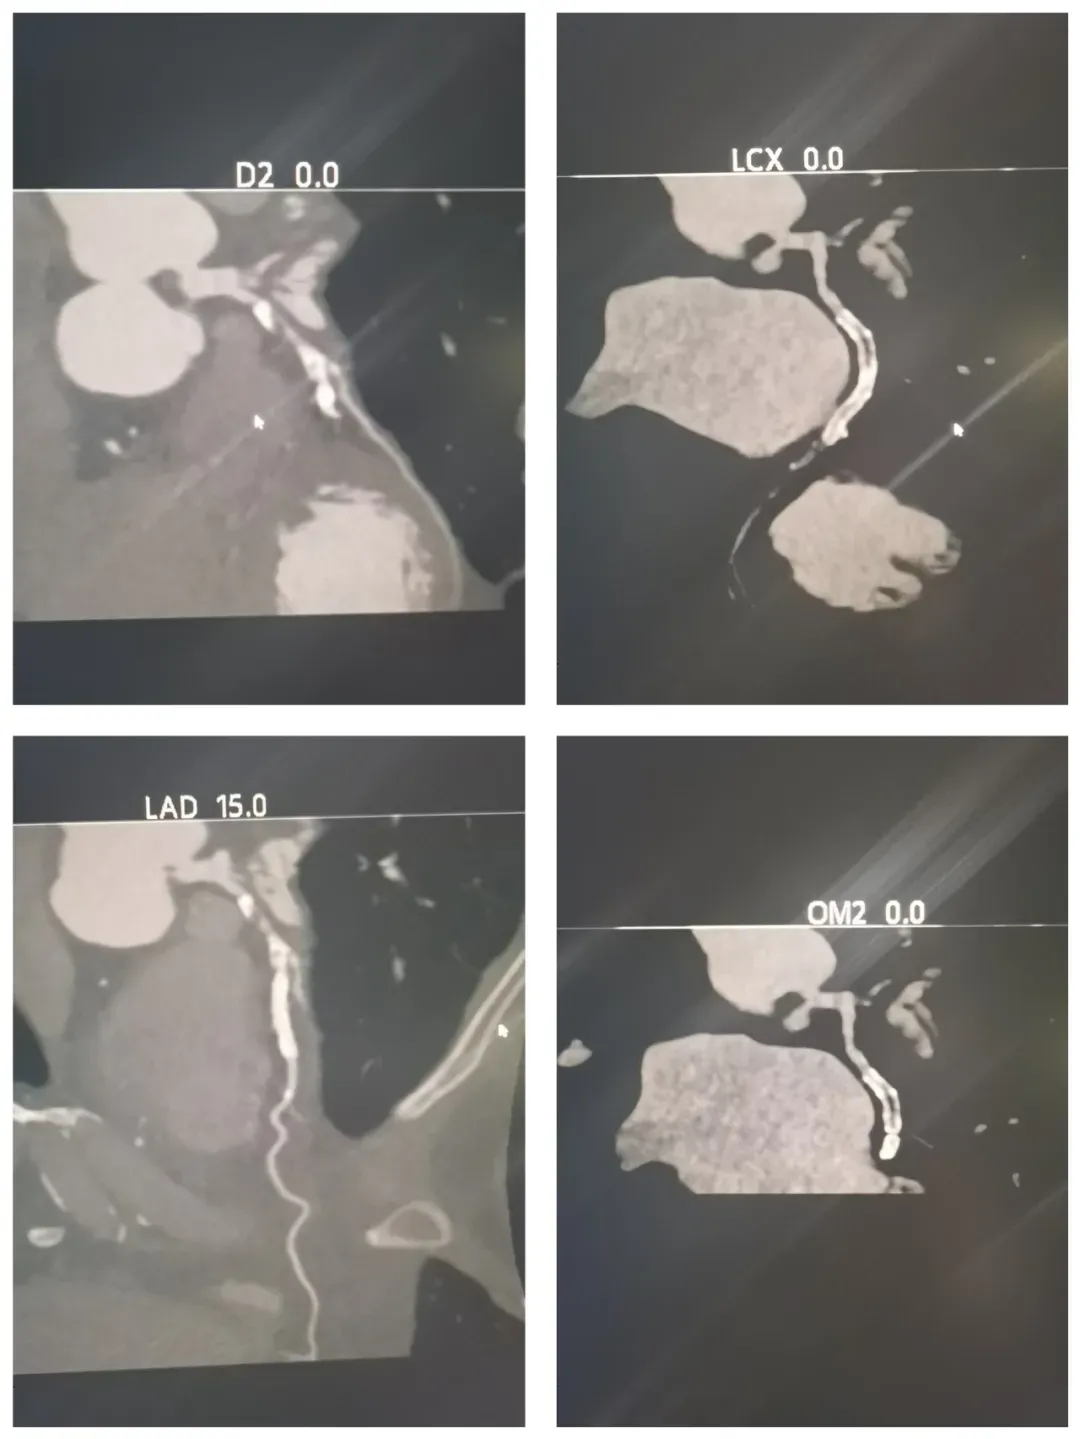

冠状动脉CTA是目前筛查和诊断冠心病的主流无创技术,通过静脉注射造影剂结合CT扫描,可清晰显示冠状动脉有无狭窄、斑块、先天畸形等病变,该技术对CT设备的扫描速度、时间分辨率和图像质量要求极高。

IMG_256 镇安县医院新购置的西门子双源CT,具有分辨率高,对患者心率快慢条件要求低,显像清晰等优势,同时辐射剂量显著降低,对比剂用量更少,检查更加安全、舒适。

设备到位后,如何让“利器”发挥最大效能成为关键。空军军医大学唐都医院放射科帮扶专家安攀,手把手教学、全流程质控,从适应症筛选、参数设定、对比剂规范,到图像重建及报告书写,将三甲医院成熟经验传授给影像团队,迅速建立起标准化冠脉CTA检查流程。目前,已成功完成检查近300例。